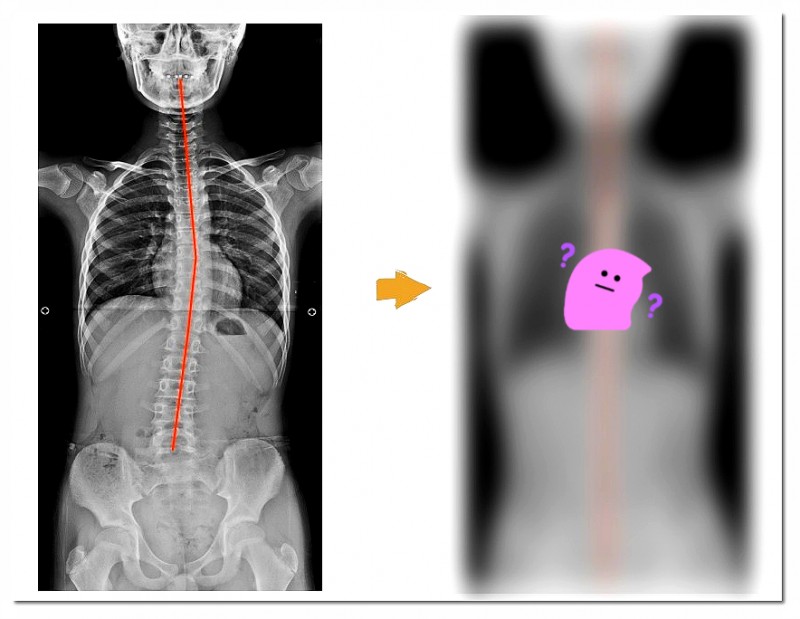

연산동체형교정을 진행할 때 저는 다양한 부분을 함께 살펴보는 편입니다.

그중 하나가 바로 보행 분석입니다.

걸을 때 발이 바닥을 딛는 방식, 체중이 이동하는 흐름을 확인합니다.

왜냐하면 ‘발’은 몸 전체를 지탱하는 기초 역할을 하기 때문입니다.

이 기초가 흔들리면 무릎, 골반, 허리까지 연쇄적으로 영향을 받을 수 있습니다.